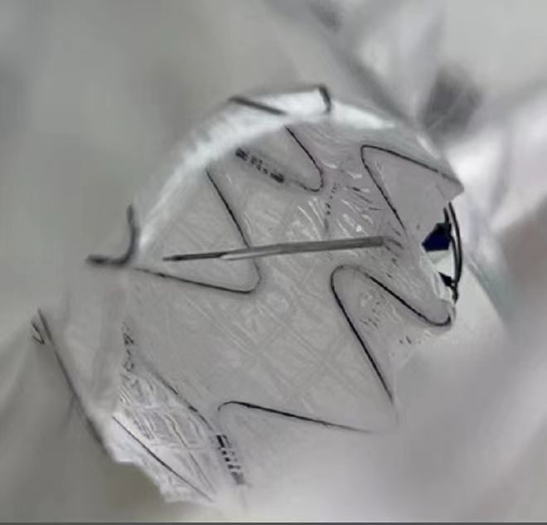

我们在两头35kg巴马公猪中完成动物实验:

成功实现弓上分支的快速、准确原位开窗;

破膜过程流畅,无分支或主动脉损伤;

取出标本可见圆形破口、支架贴合良好,证实技术可行性。

动物实验

巴马公猪35kg

标本